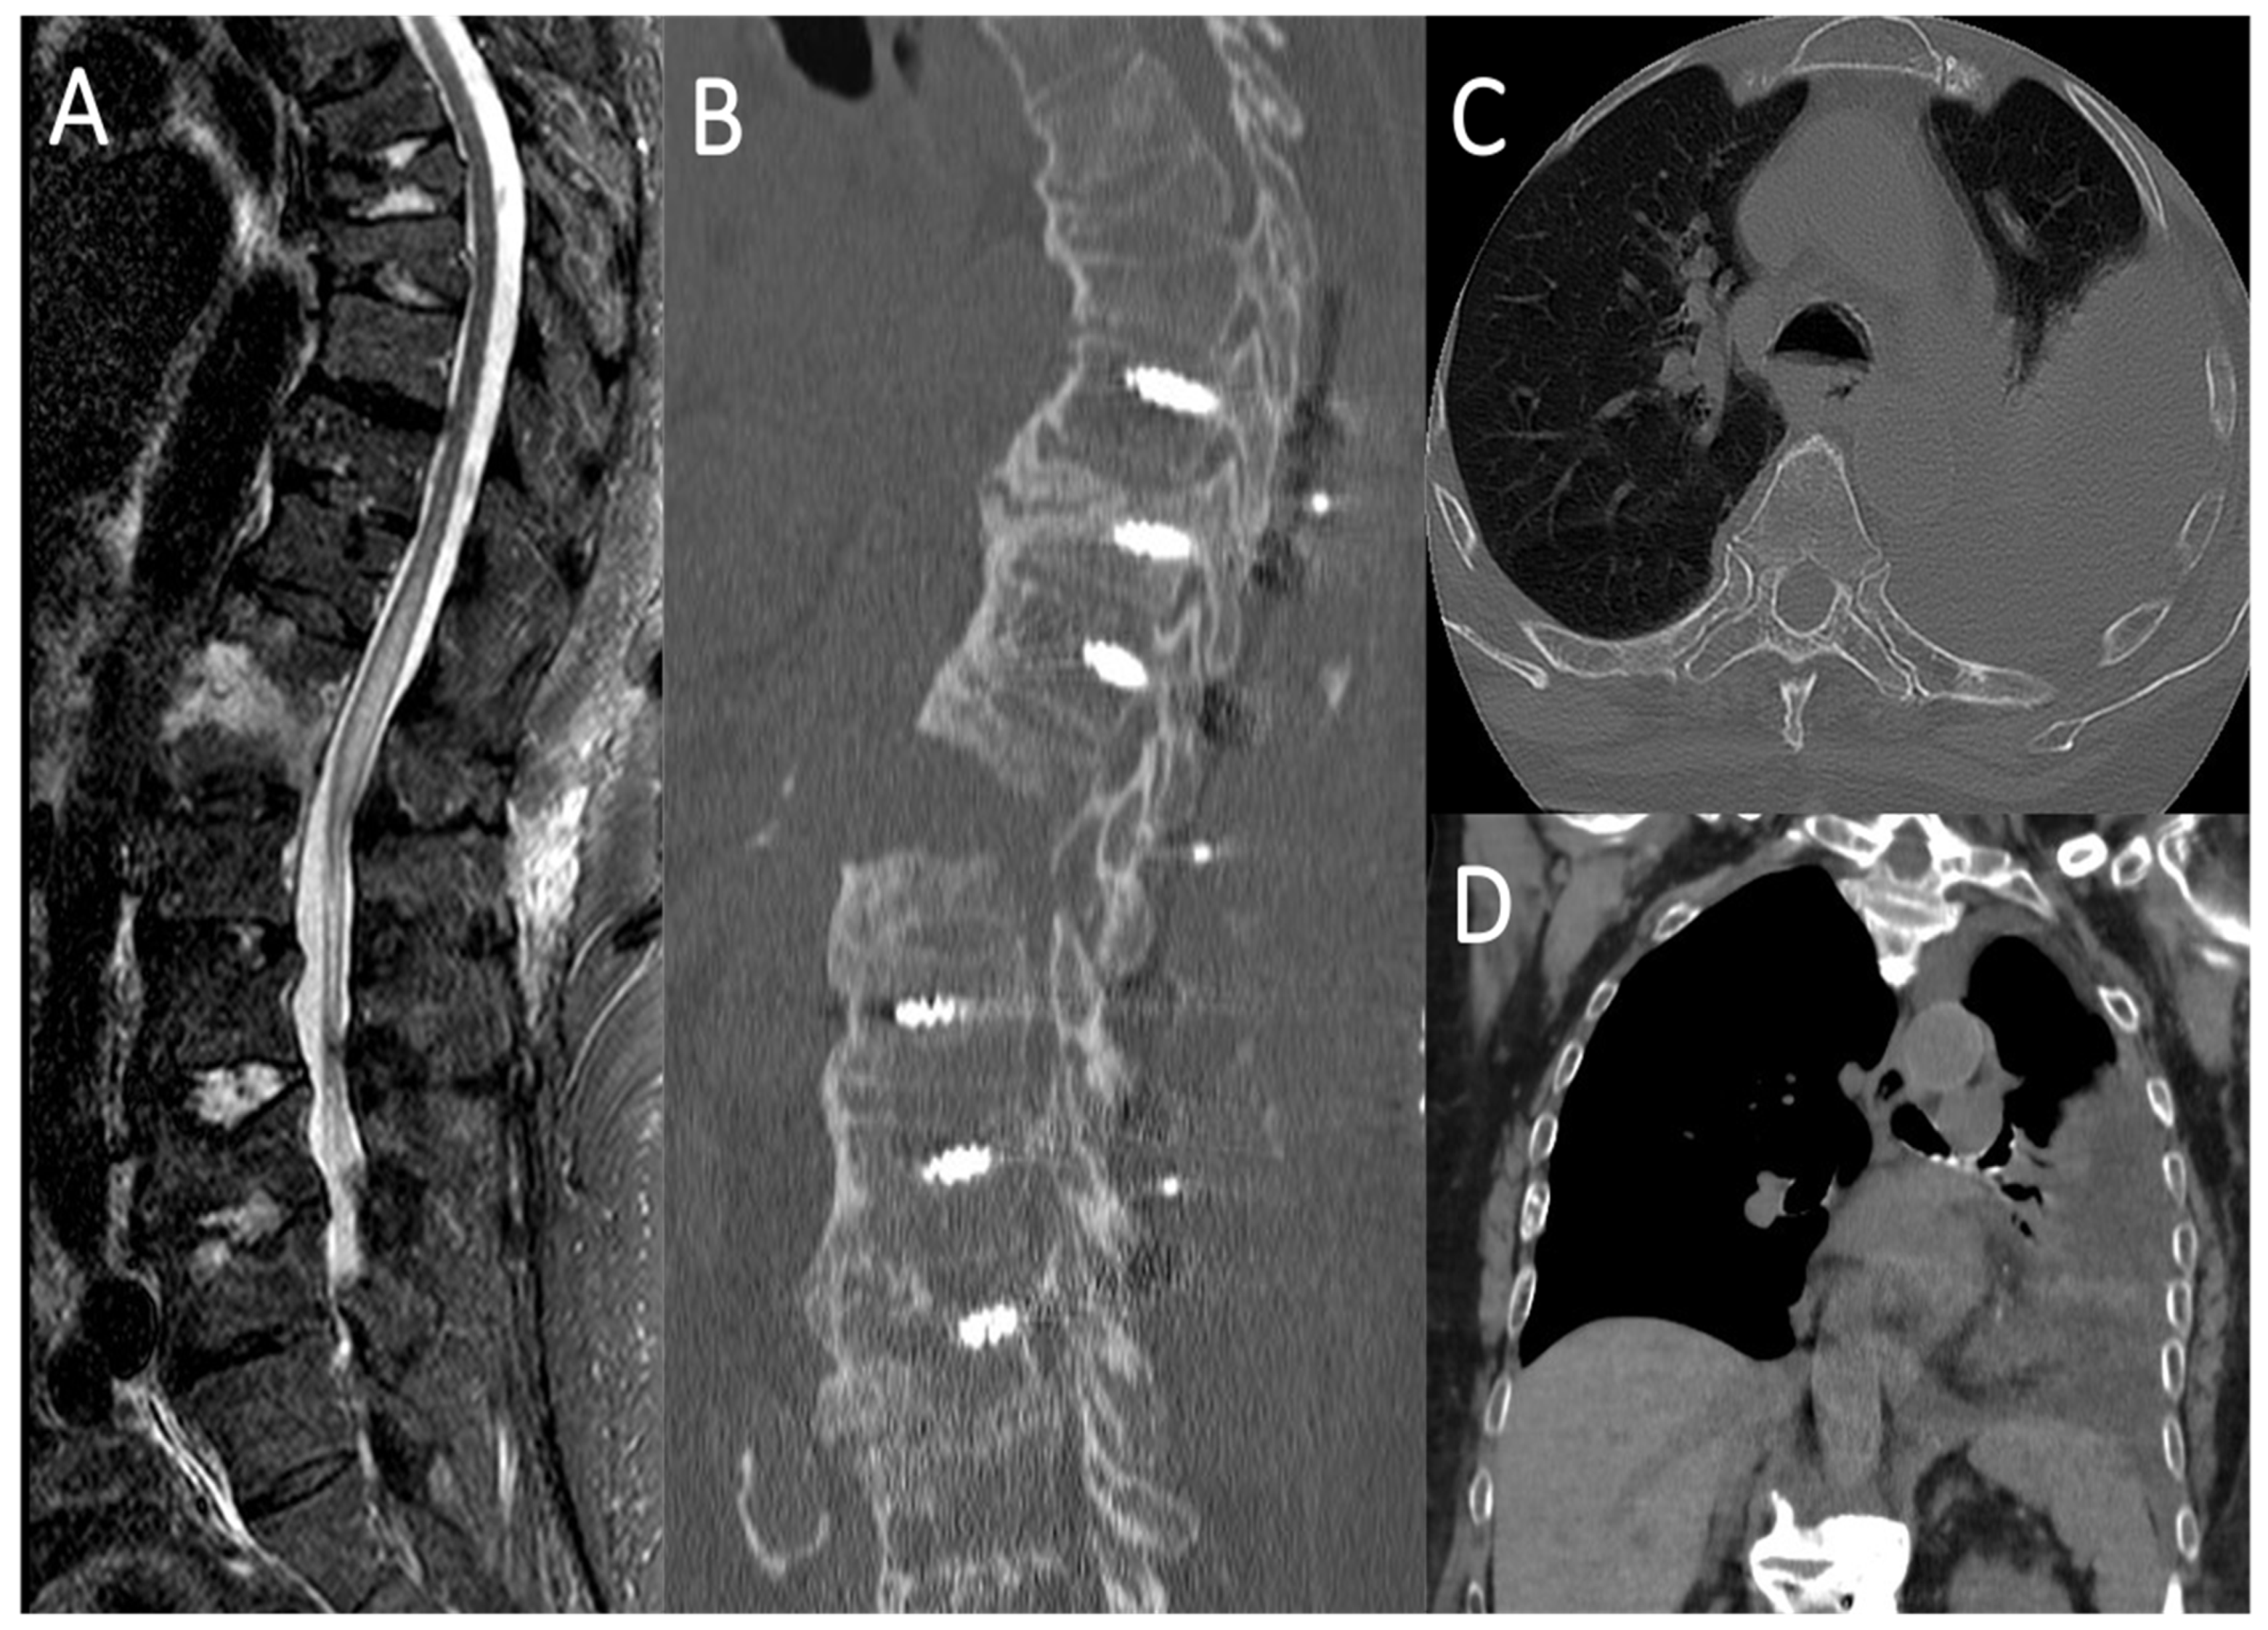

4.1. Case Report 1: Coating

4.2. Case Report 2: Coating Straddling Nerve Roots

- Lofrese, G.; Cultrera, F.; Visani, J.; Scerrati, A.; Mongardi, L.; Donati, R.; Tosatto, L.; De Bonis, P. Chylothorax in spine fractures: A rarely reported complication? Literature review with an example case. J. Trauma Acute Care Surg. 2020, 89, e140–e146. [Google Scholar] [CrossRef]